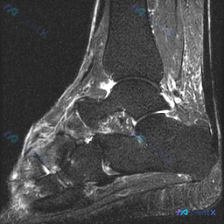

这是一张踝关节MRI矢状位T2加权图像,T2序列对液体和软组织水肿显示敏感,以下是具体异常发现:

- 距下关节及跗骨窦区域:距骨下方、跟骨上方的关节间隙及周围软组织可见弥漫性高信号,提示明显积液或炎性水肿;距骨和跟骨关节面下骨质可见边界模糊的局部高信号,提示骨髓水肿或骨侵蚀性改变,关节面不平整;关节间隙内存在明显积液信号,符合距下关节滑膜炎或严重退变/损伤表现。

- 胫距踝关节:前间隙可见少量积液,关节面骨质形态尚可,前踝关节囊区域存在轻度软组织水肿。

- 肌腱韧带:跟腱走行连续无明显断裂,周围脂肪间隙信号稍模糊,提示轻度周围炎性改变;长屈肌腱显示无明显异常。

- 中足区域:距舟关节及楔骨区域可见局部骨髓高信号和软组织水肿,提示病变不止累及后足。